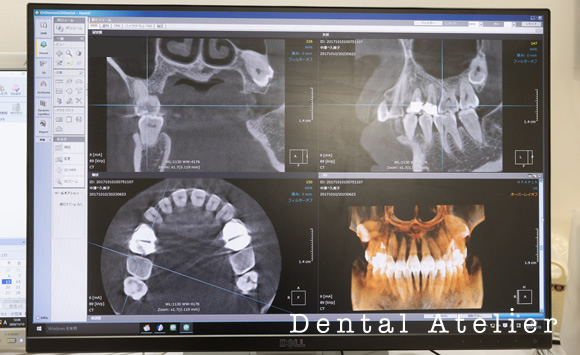

(3)CTスキャン

複雑な形態をした根っこの隅々まで細菌に感染した歯質や神経を除去する必要がありますが、従来のレントゲン画像だけでは 病変や歯のヒビを確実に把握することは困難です。

CTによる立体的な3次元の画像を確認することによって、全ての情報がより明確になり、従来のレントゲンでは見えなかった、 見落としてしまっていた虫歯や根の感染を把握します。